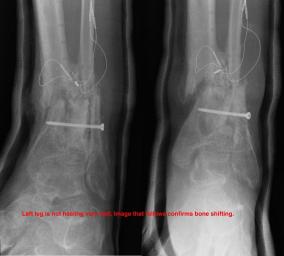

Postoperative (12th) images of left ankle

The images displayed here were created at various appointments following surgery performed by Dr. Daniel Saunders. In the X-Ray you can see

where Dr. Saunders has removed the fibula plate, joined the tibia and fibula with a screw, built-up the area of the tibia where previously

there was considerable absence of bone and lastly added the EBI OsteoGen-M Bone Stimulator (dual lead). The photos show the left side site

where the fibula plate was removed, the top site where donor bone, bone filler material and the stimulator were added and the right side

where the tissue has burst because of swelling. Liam was placed on an IV drip of Vancomycin following surgery to combat the potential onset

of Osteomyelitis. The image of the cast includes the fibula plate that was removed during surgery. The next images were taken later and show

that the staples and stitches were removed. In one of the images, you can see Liam's wife Madeline helping with leg cleanup and in one image

can be seen the EBI representative after being put to work (holding up the left leg while the latest cast cures) by Dr. Saunders. Later shots show

a healing tissue burst site with some overgrowth and Dr. Saunders cauterizing the overgrowth. Bones shifting too much (shown in X-Rays). The

last images are of the left ankle prior to the 13th surgery.